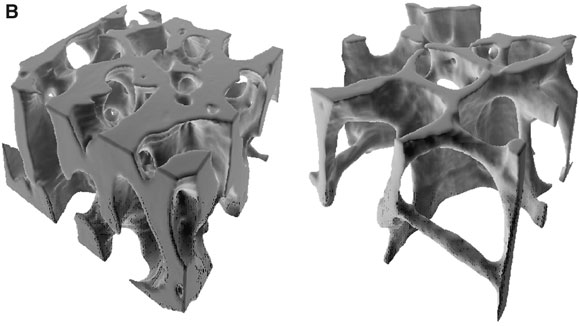

2: Bone in osteoporosis

A. Imbalance between bone formation and resorption leads to trabecular thinning (left) and eventual loss of trabecular connectivity (right) (reprinted from Mosekilde,6 with permission from Elsevier).

B. Loss of trabeculae and thinning (right) reduce cross-sectional area so that loads on bone are relatively greater (reprinted from Keaveny et al 8 with permission from Annual Review of Biomedical Engineering [www.annual.reviews.org]).